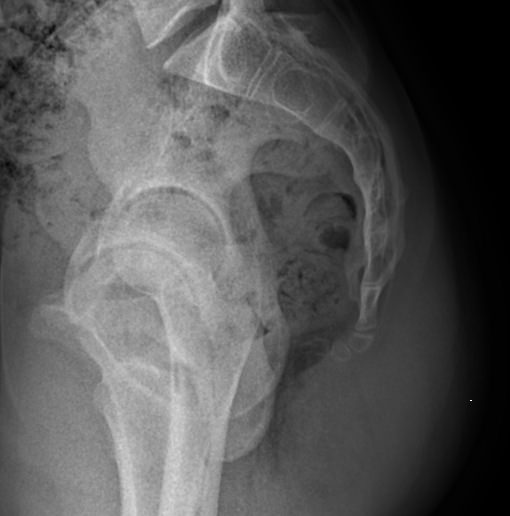

• Отклонение копчика кпереди по отношению к крестцу;

• Изменения в крестцово-копчиковом суставе: уменьшение рентгеновской щели, субхондральный склероз;

• Переломы;

• Новообразования.